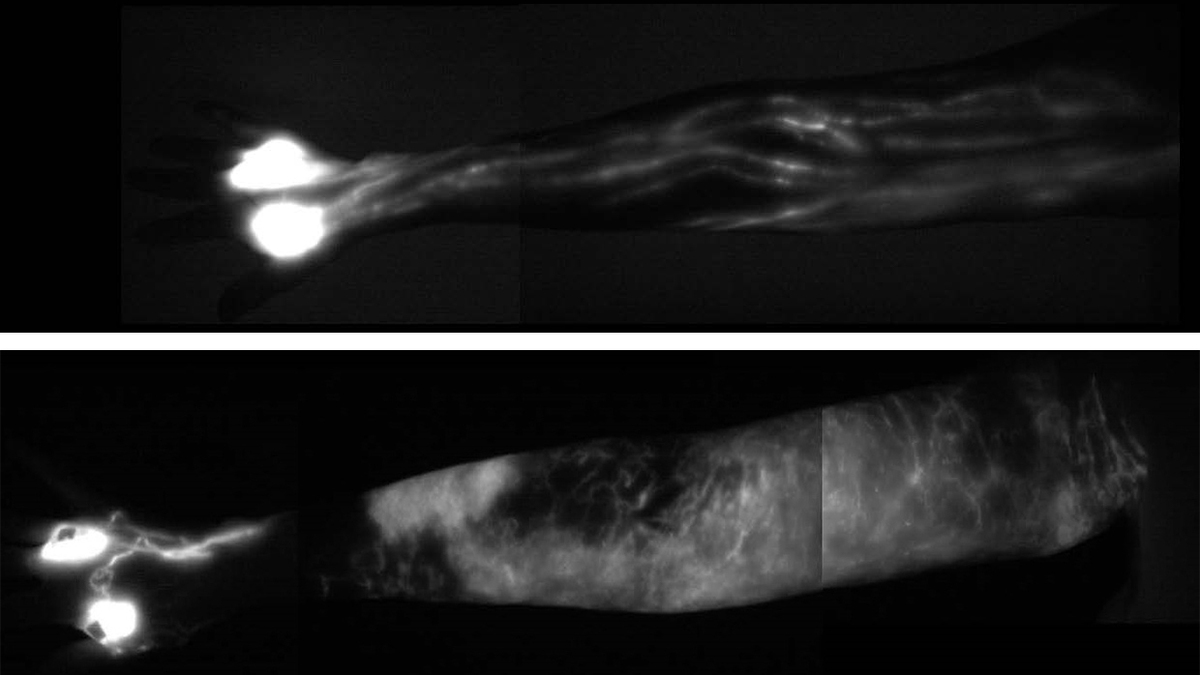

The image of a normal upper arm (top) shows the delicate network of healthy lymph vessels. In the lower image of a patient with lymphedema, a collection of lymph fluid, in white, has made the arm swell. Courtesy of Memorial Sloan Kettering Cancer Center hide caption

The image of a normal upper arm (top) shows the delicate network of healthy lymph vessels. In the lower image of a patient with lymphedema, a collection of lymph fluid, in white, has made the arm swell.

Courtesy of Memorial Sloan Kettering Cancer Center"It's like an angiogram of the heart — you can see any disease, any scarring." Even in areas that haven't yet produced obvious pain or swelling.